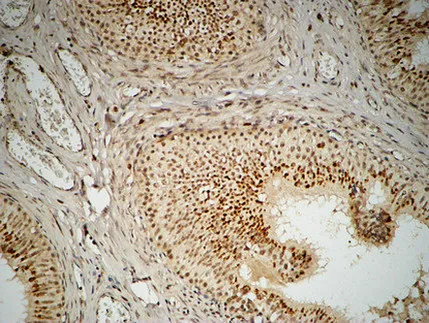

FOXP1 Rabbit Polyclonal Antibody

Cat: APRab11113

Size1:50μl Price1:$118

Size2:100μl Price2:$220

Size3:500μl Price3:$980

Size2:100μl Price2:$220

Size3:500μl Price3:$980